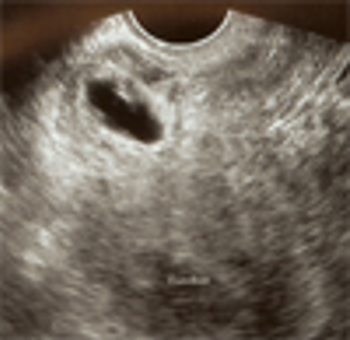

Implantation in the scar of a previous Cesarean is thought to be the rarest of ectopic pregnancies. With the increasing numbers of Cesareans performed, scar implantation may become more frequent as well. We present an illustrative case.